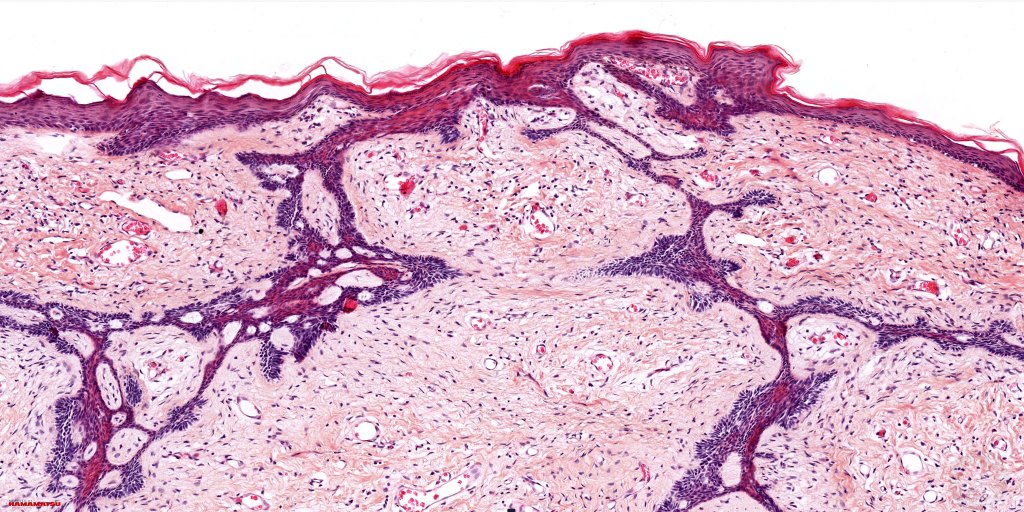

Histological features

•Multifocal origin from epidermis

•Anastomosing basaloid, narrow epithelial strands associated with a prominent fibrous (sometimes myxoid) stroma

•Peripheral palisade